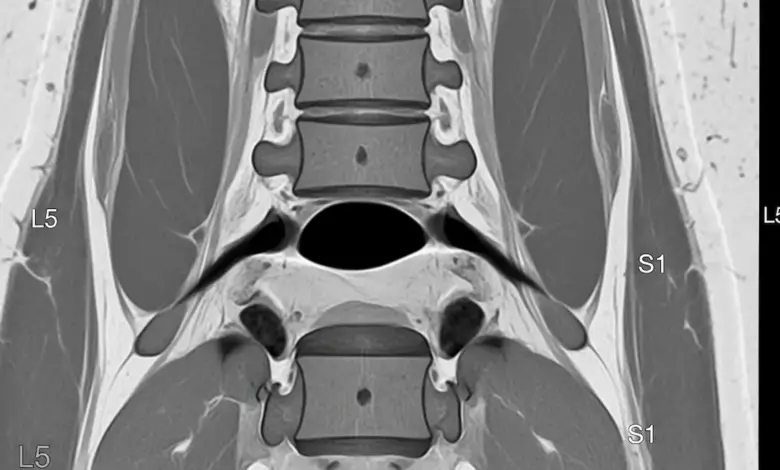

A expressão discopatia degenerativa L5 S1 com protusão discal descreve o desgaste do disco entre a última vértebra lombar e o sacro, somado a um abaulamento do disco que pode irritar raízes nervosas.

- Ressonância magnética: método de eleição para visualizar a degeneração e protusão.

A intensidade da dor nem sempre corresponde ao tamanho da protusão. O laudo precisa ser interpretado junto do exame clínico e do contexto funcional do paciente.